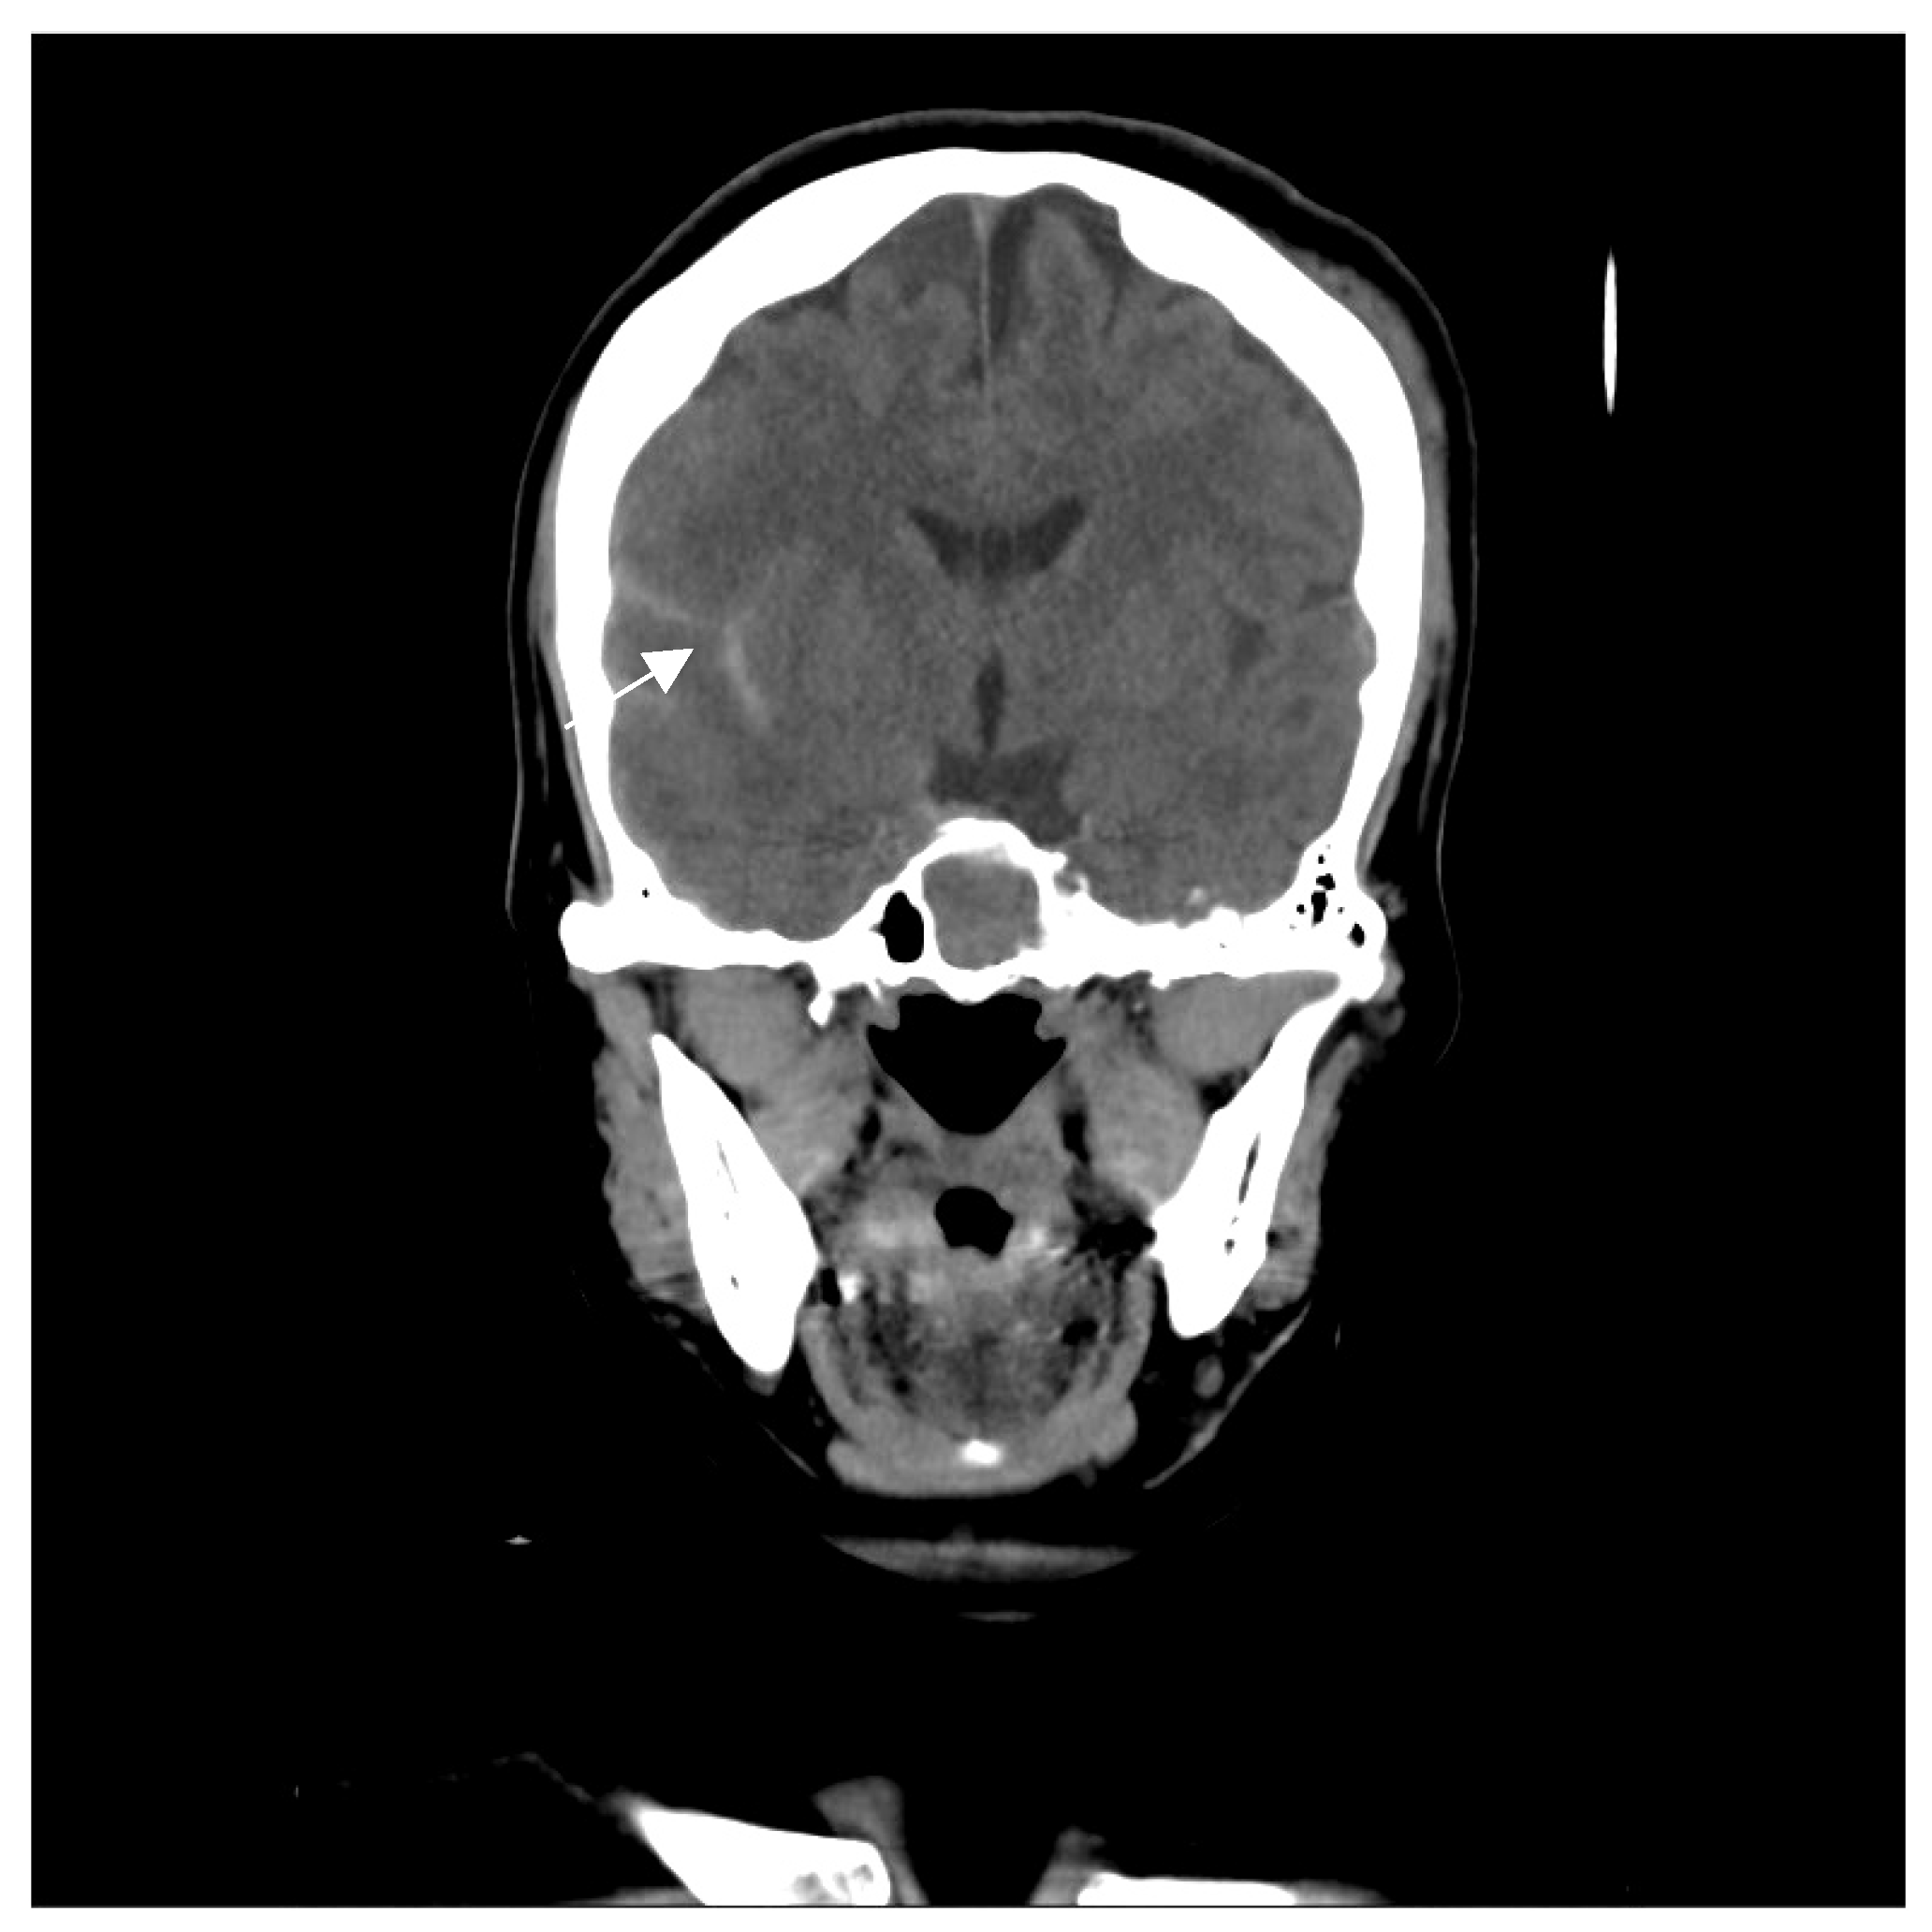

A 46-year-old woman with medically controlled hyperthyroidism was a victim of a motor vehicle accident on the road. The accident led to poor consciousness with Glasgow Coma Scale (GCS) level at E4V1M4, nasal bleeding, and left otorrhea in the patient. A brain computed tomography (CT) scan (Figure 1) showed a small subdural hematoma over the right temporal lobe, right Sylvian subarachnoid hemorrhage, and a right sellar floor fracture with sphenoid sinus hematoma upon arrival at the emergency room. The patient underwent right intracranial pressure monitor insertion for further monitoring and intensive care. Fortunately, the severity of traumatic brain injury did not progress. She gradually regained consciousness 3 days post-trauma. However, she complained of a progressive right eye floater and flash 4 weeks later, so she visited an ophthalmologist for further evaluation. Initial examination revealed right eye proptosis and conjunctival vessels engorgement, without chemosis, or tinnitus in the right ear. (Figure 2a) Rapidly progressive severe right eye exophthalmos, audible bruits, and chemosis (Figure 2b) developed within several days, highly suggesting right carotid cavernous fistula. The visual acuity and intraocular pressure data before treatment and one month post-treatment of the CCF are listed in Table 1. In addition, she became unconscious (GCS E3V2M5) and had left limb hemiplegia. A brain magnetic resonance imaging (MRI) (Figure 3a) disclosed engorgement of the right SOV and swelling of right orbital cavity (the MRI protocol we used is listed below in Table 2). In addition, high T2-weighted imaging signal changes were observed in the right corpus striatum (Figure 3b), right insular lobe, right inferior frontal lobe, right medial temporal lobe, midbrain, and pons (Figure 3c), which indicate perifocal brain edema.

Figure 1.

The figure reveals a small subdural hematoma over the right temporal lobe (arrow), sylvian subarachnoid hemorrhage, and right sellar floor fracture with sphenoid sinus hematoma.